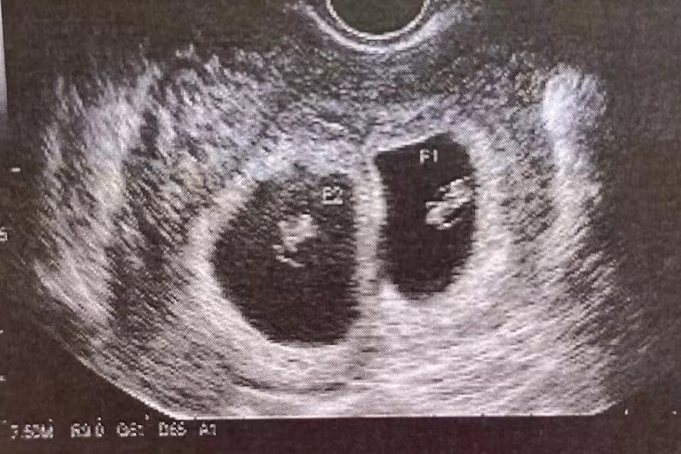

2、异卵双胞胎

异卵双胞胎是由一定的条件所致,母亲在一个排卵周期内排出两颗卵子,由两个卵子分别受精形成的两个受精卵,以后分别发育成两个胎儿。一般在早期的B超检查显示为两个妊娠囊、两个胎心、两个胎芽。